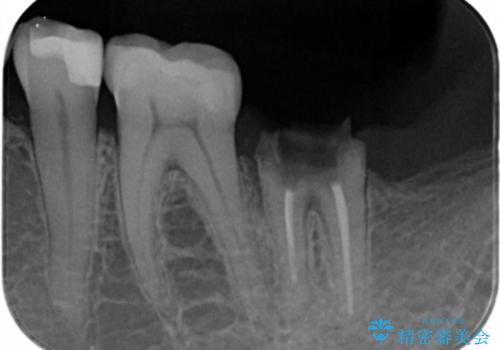

X線検査を行ったところ、セラミッククラウン下に虫歯が再発し、歯の破折も認めました。

X線を撮ることで、外から見てもわからない、歯の問題点をより正確に把握することができます。